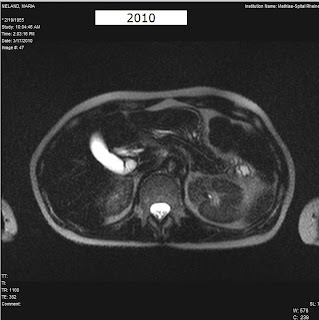

An hour glass gallbladder is shaped like an hour glass and will look something like this in an MRI